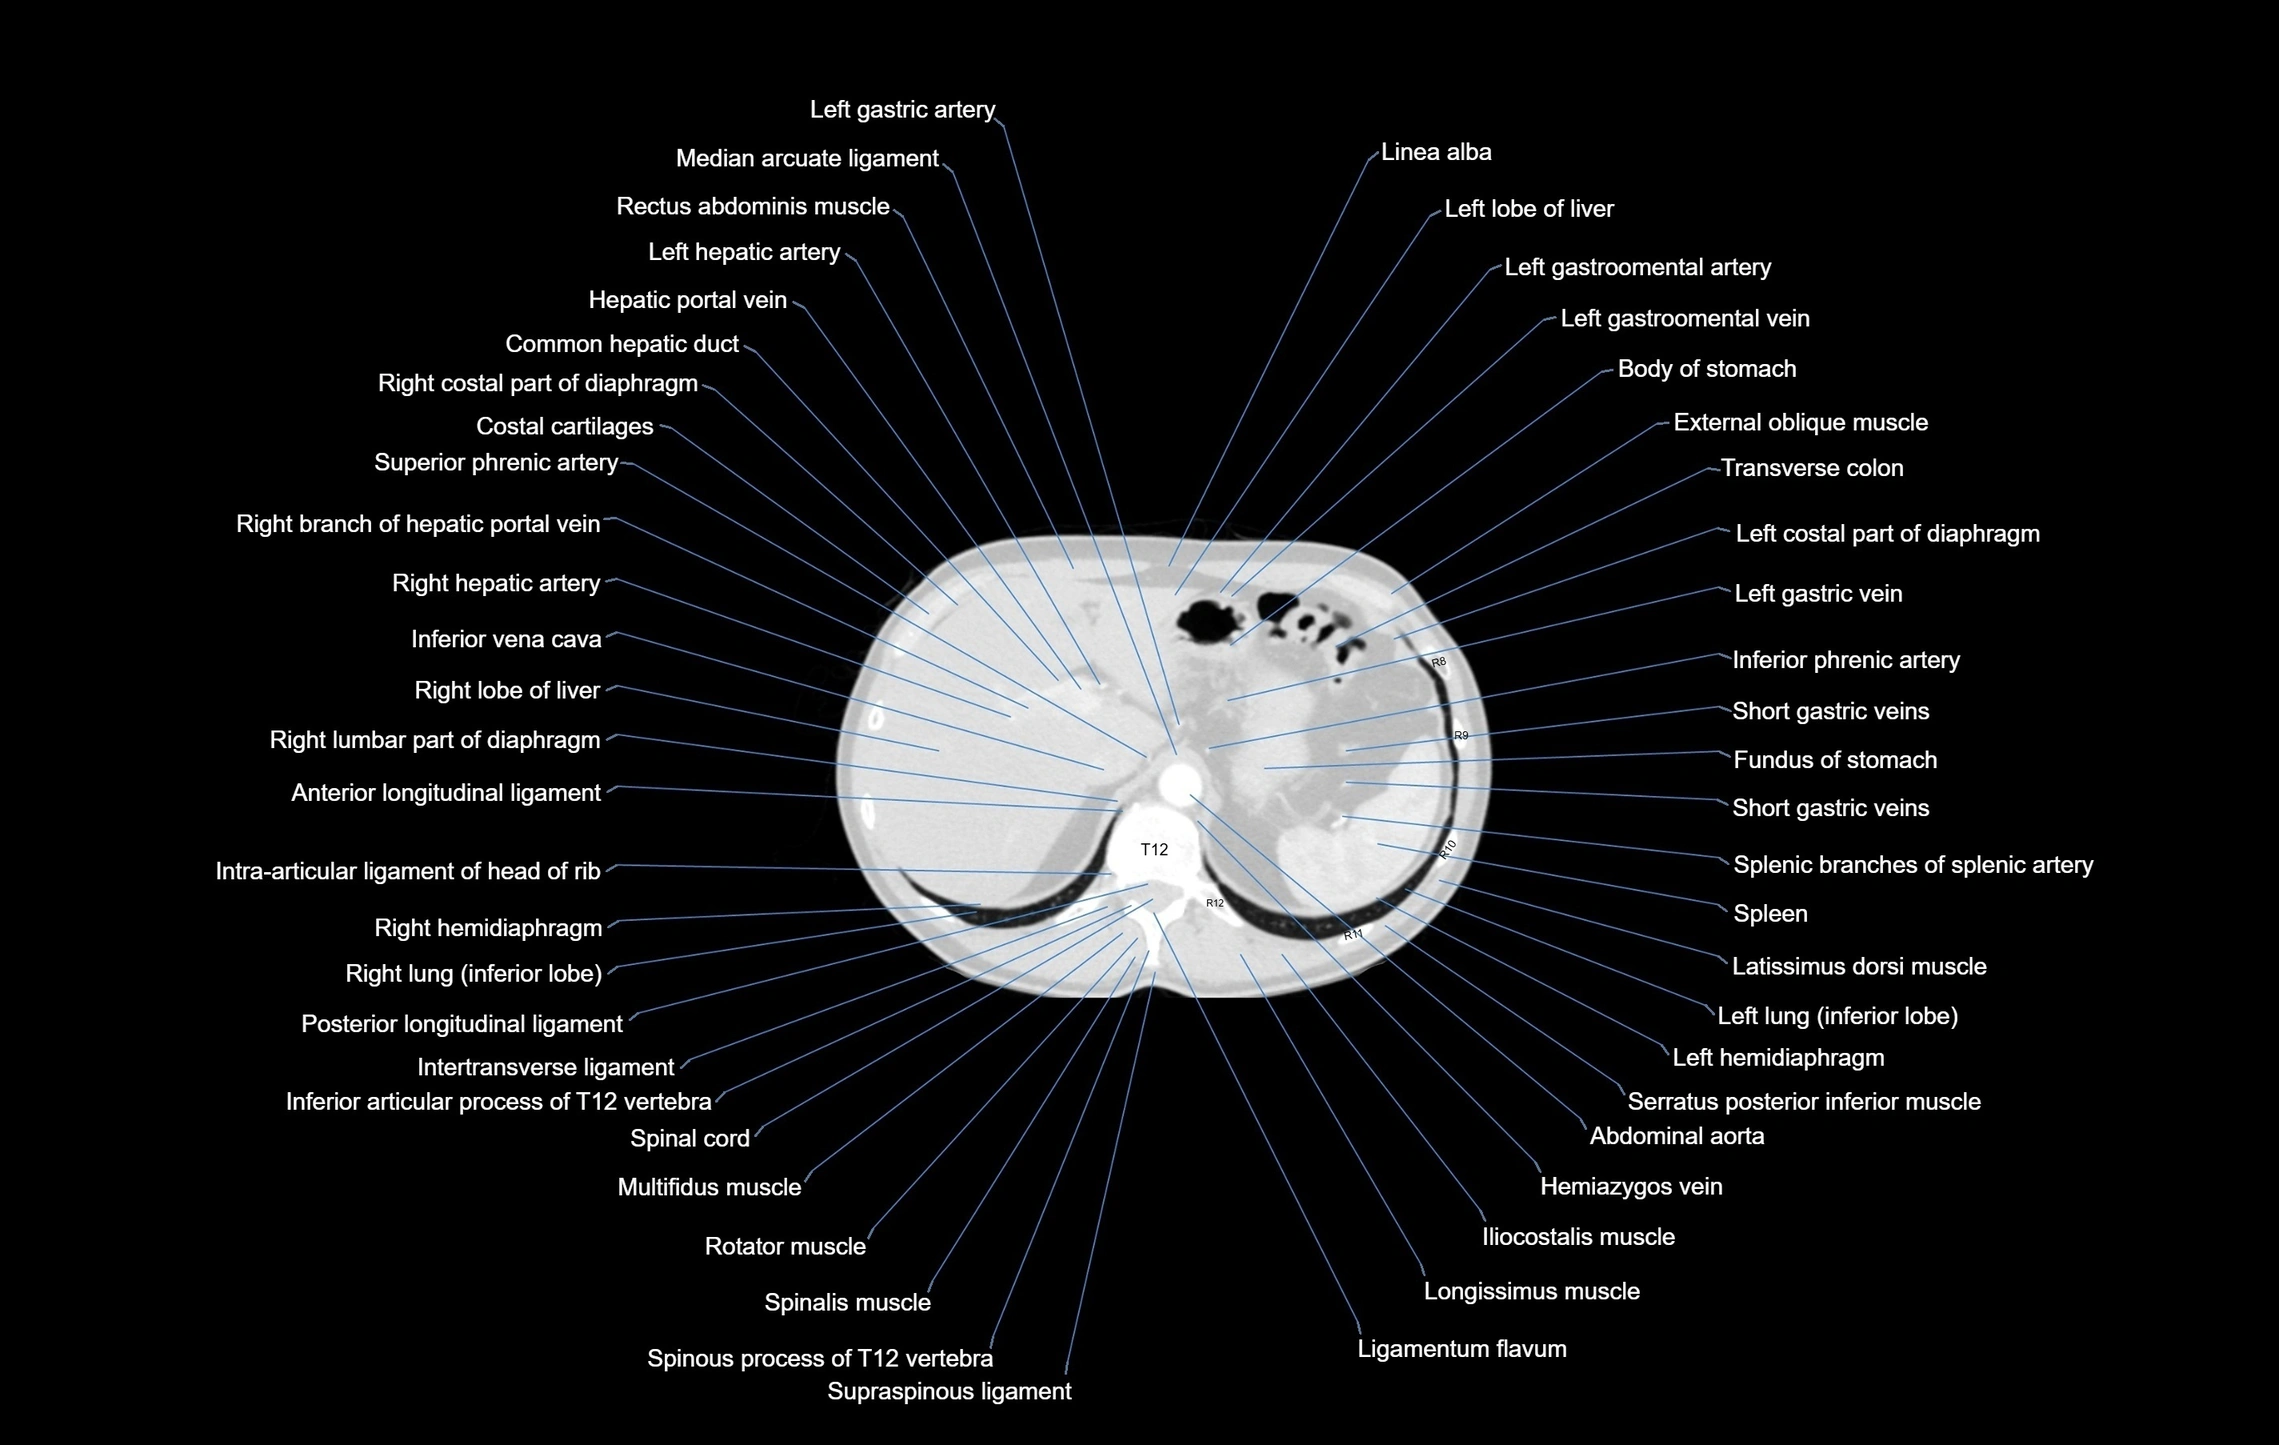

- Abdominal aorta

- Anterior longitudinal ligament

- Costal cartilages

- External oblique muscle

- Hemiazygos vein

- Hepatic portal vein

- Inferior phrenic artery

- Inferior vena cava

- Intertransverse ligament

- Intra-articular ligament of head of rib

- Latissimus dorsi muscle

- Left gastric artery

- Left hemidiaphragm

- Left lobe of liver

- Left lung (inferior lobe)

- Median arcuate ligament

- Multifidus muscles

- Posterior longitudinal ligament

- Rectus abdominis muscle

- Right lobe of liver

- Right lung (inferior lobe)

- Serratus posterior inferior muscle

- Short gastric veins

- Spleen

- Splenic branches of splenic artery

- Splenic vein

- Superior phrenic artery

- Transverse colon